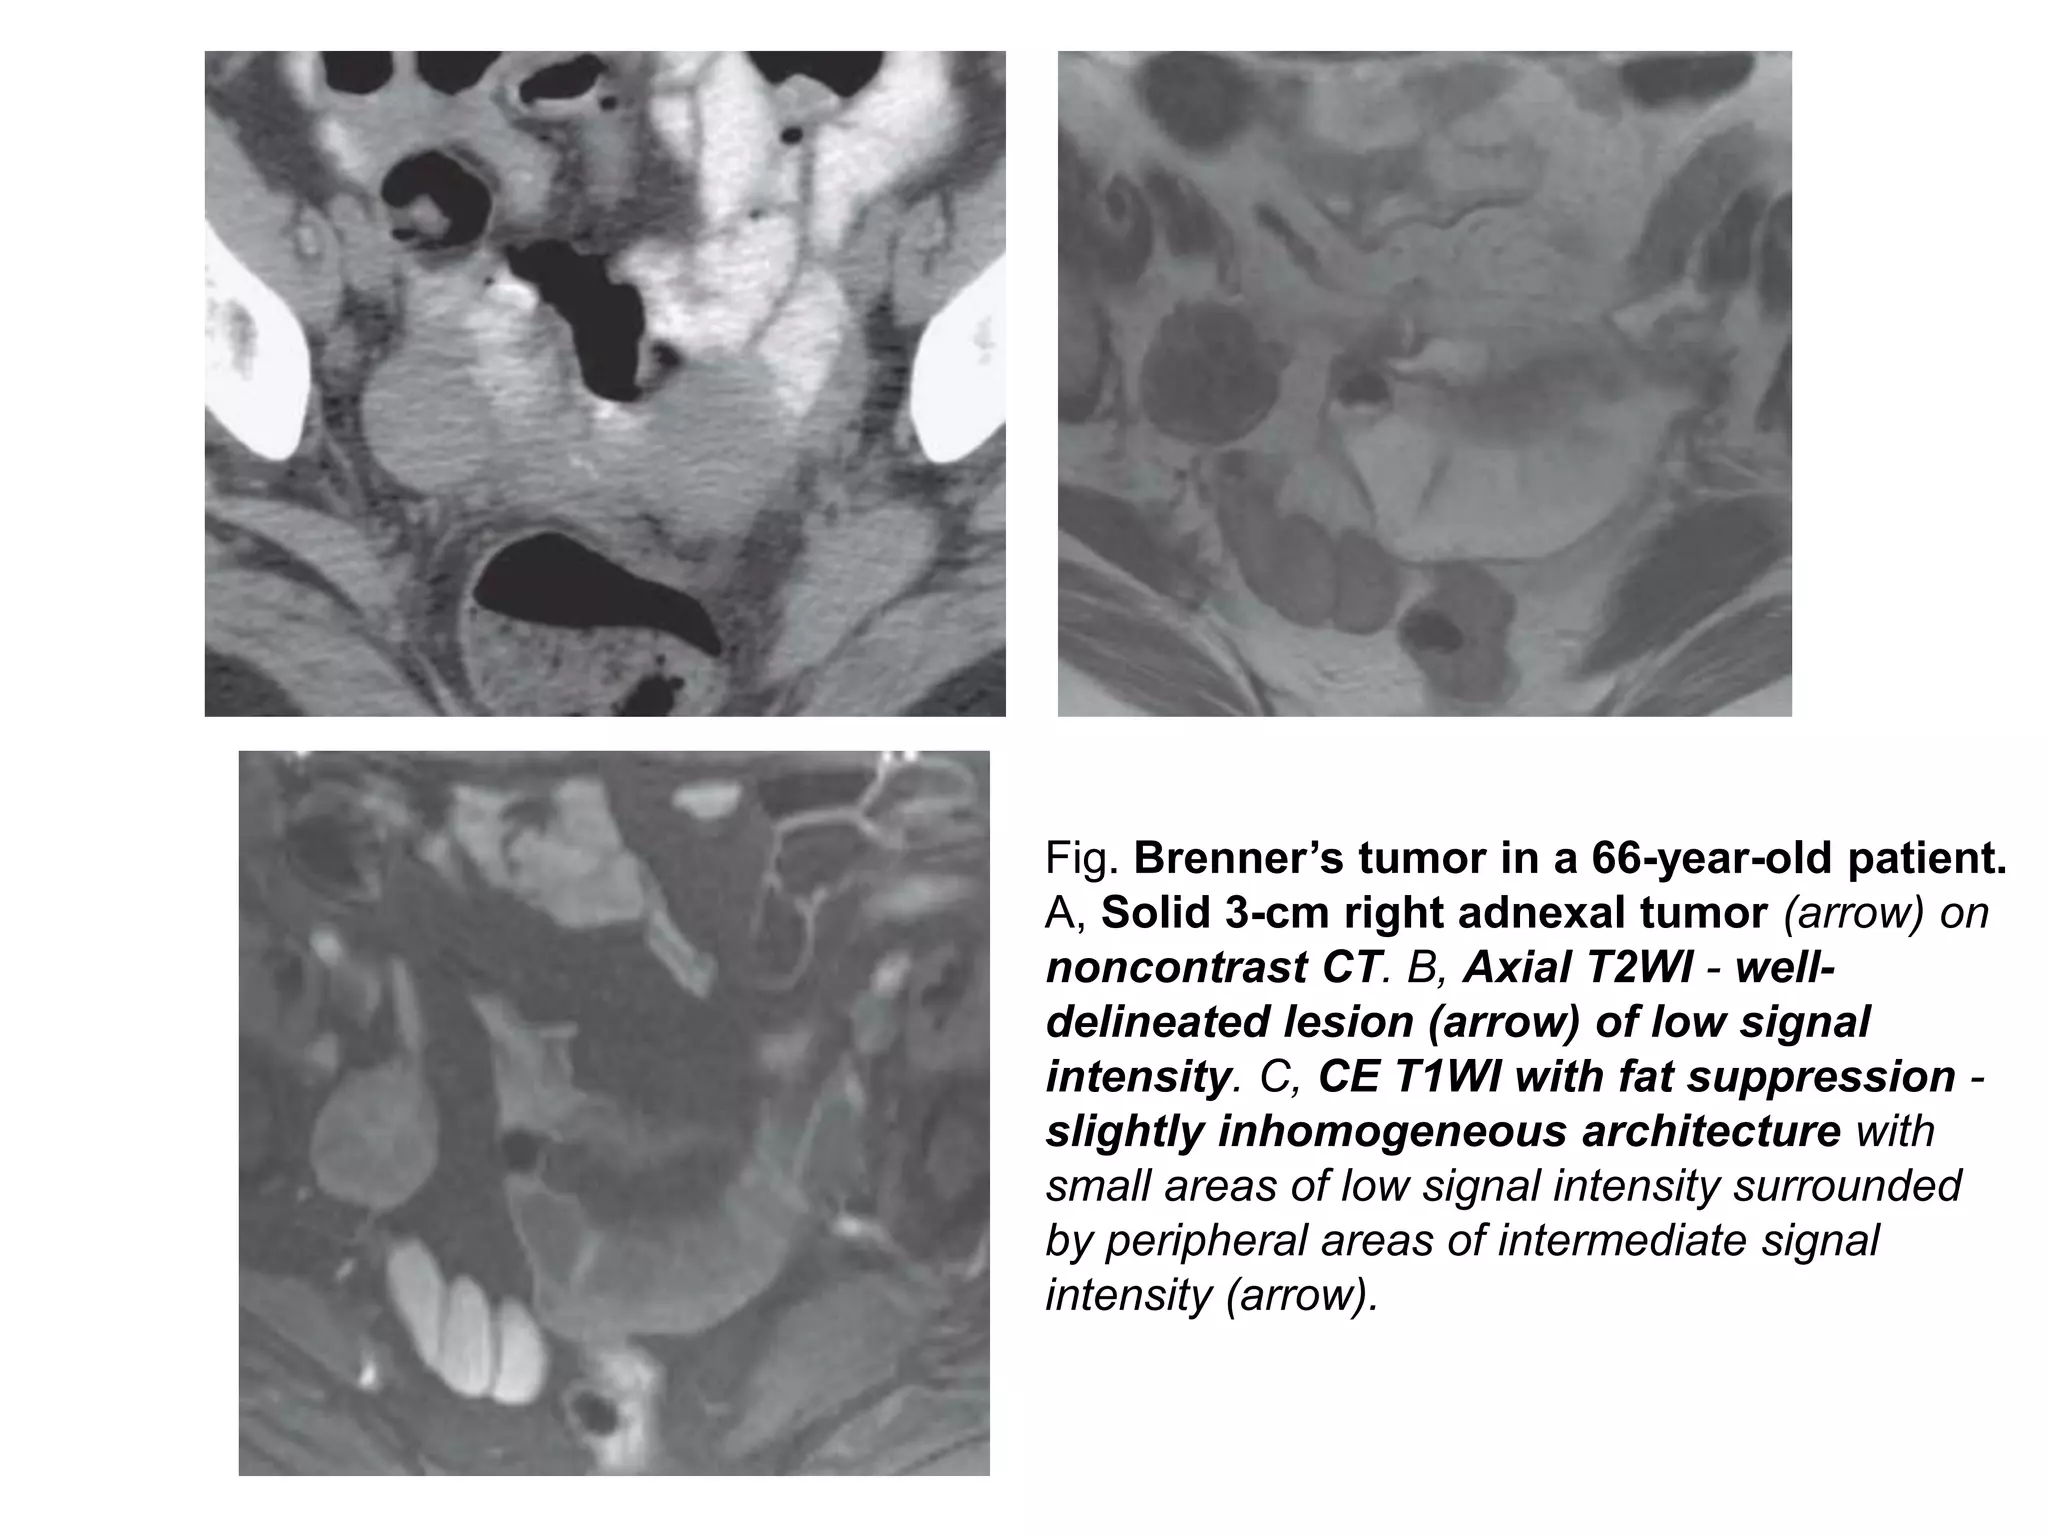

Fig. Brenner’s tumor in a 66-year-old patient.

A, Solid 3-cm right adnexal tumor (arrow) on

noncontrast CT. B, Axial T2WI - well-

delineated lesion (arrow) of low signal

intensity. C, CE T1WI with fat suppression -

slightly inhomogeneous architecture with

small areas of low signal intensity surrounded

by peripheral areas of intermediate signal

intensity (arrow).

Brenner’s tumors • Rarelesions (2% to 3% of all ovarian tumors), and are composed of transitional cells and dense stroma. • Rarely malignant, usually less than 2 cm, and typically discovered incidentally. • Appears as either a multilocular cystic mass with a solid component or as a small predominately solid mass - mild or moderate enhancement at CT. • Extensive calcification within the solid component is often present. • MRI: dense stroma - low T2-weighted signal similar to that of a fibroma.

• 65.

Fig. Brenner’s tumorin a 66-year-old patient. A, Solid 3-cm right adnexal tumor (arrow) on noncontrast CT. B, Axial T2WI - well- delineated lesion (arrow) of low signal intensity. C, CE T1WI with fat suppression - slightly inhomogeneous architecture with small areas of low signal intensity surrounded by peripheral areas of intermediate signal intensity (arrow).